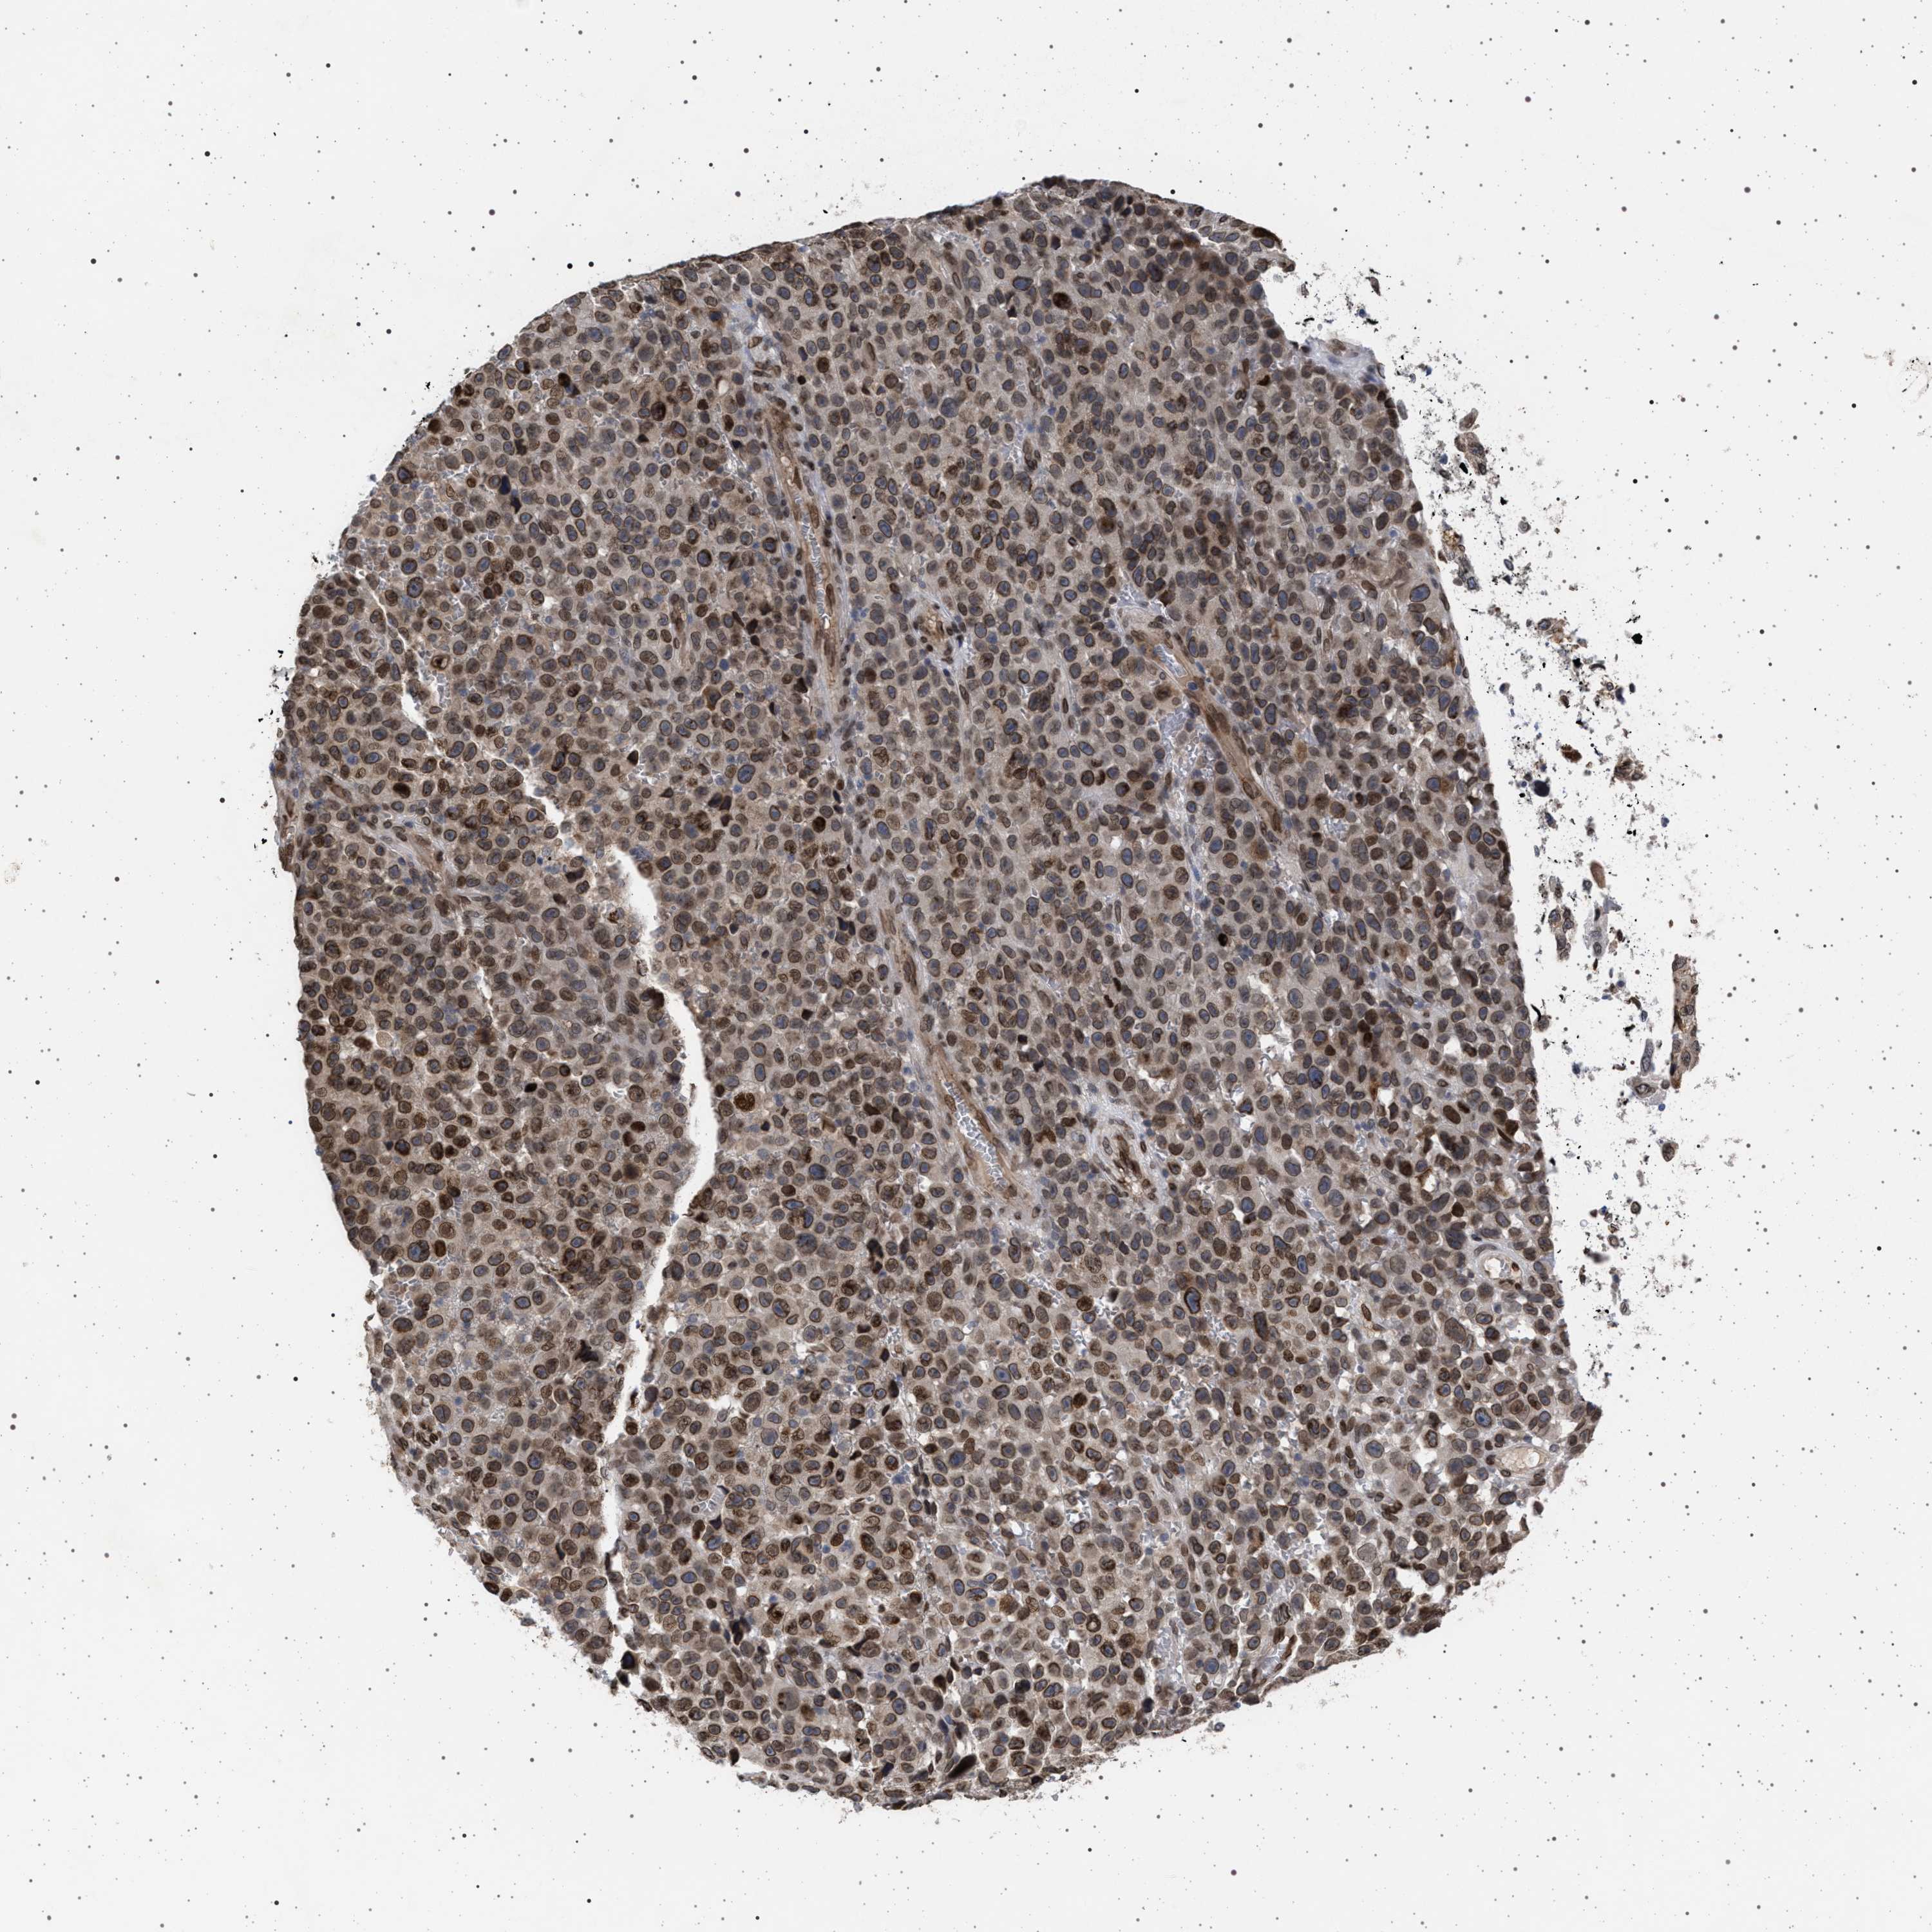

SKIN CANCER - Protein expressioni

A mouse-over function shows sample information and annotation data. Click on an image to view it in a full screen mode. Samples can be filtered based on level of antibody staining by selecting one or several of the following categories: high, medium, low and not detected. The assay and annotation is described here.

Each image is clickable and will lead to virtual microscopy that enables deeper exploration of all samples and also displays staining intensity scores, fraction scores and subcellular localization as well as patient and tissue information for each sample.

Antibody HPA019486

Staining

High

Intensity

Strong

Quantity

>75%

Location

Nuclear

Basal cell carcinoma